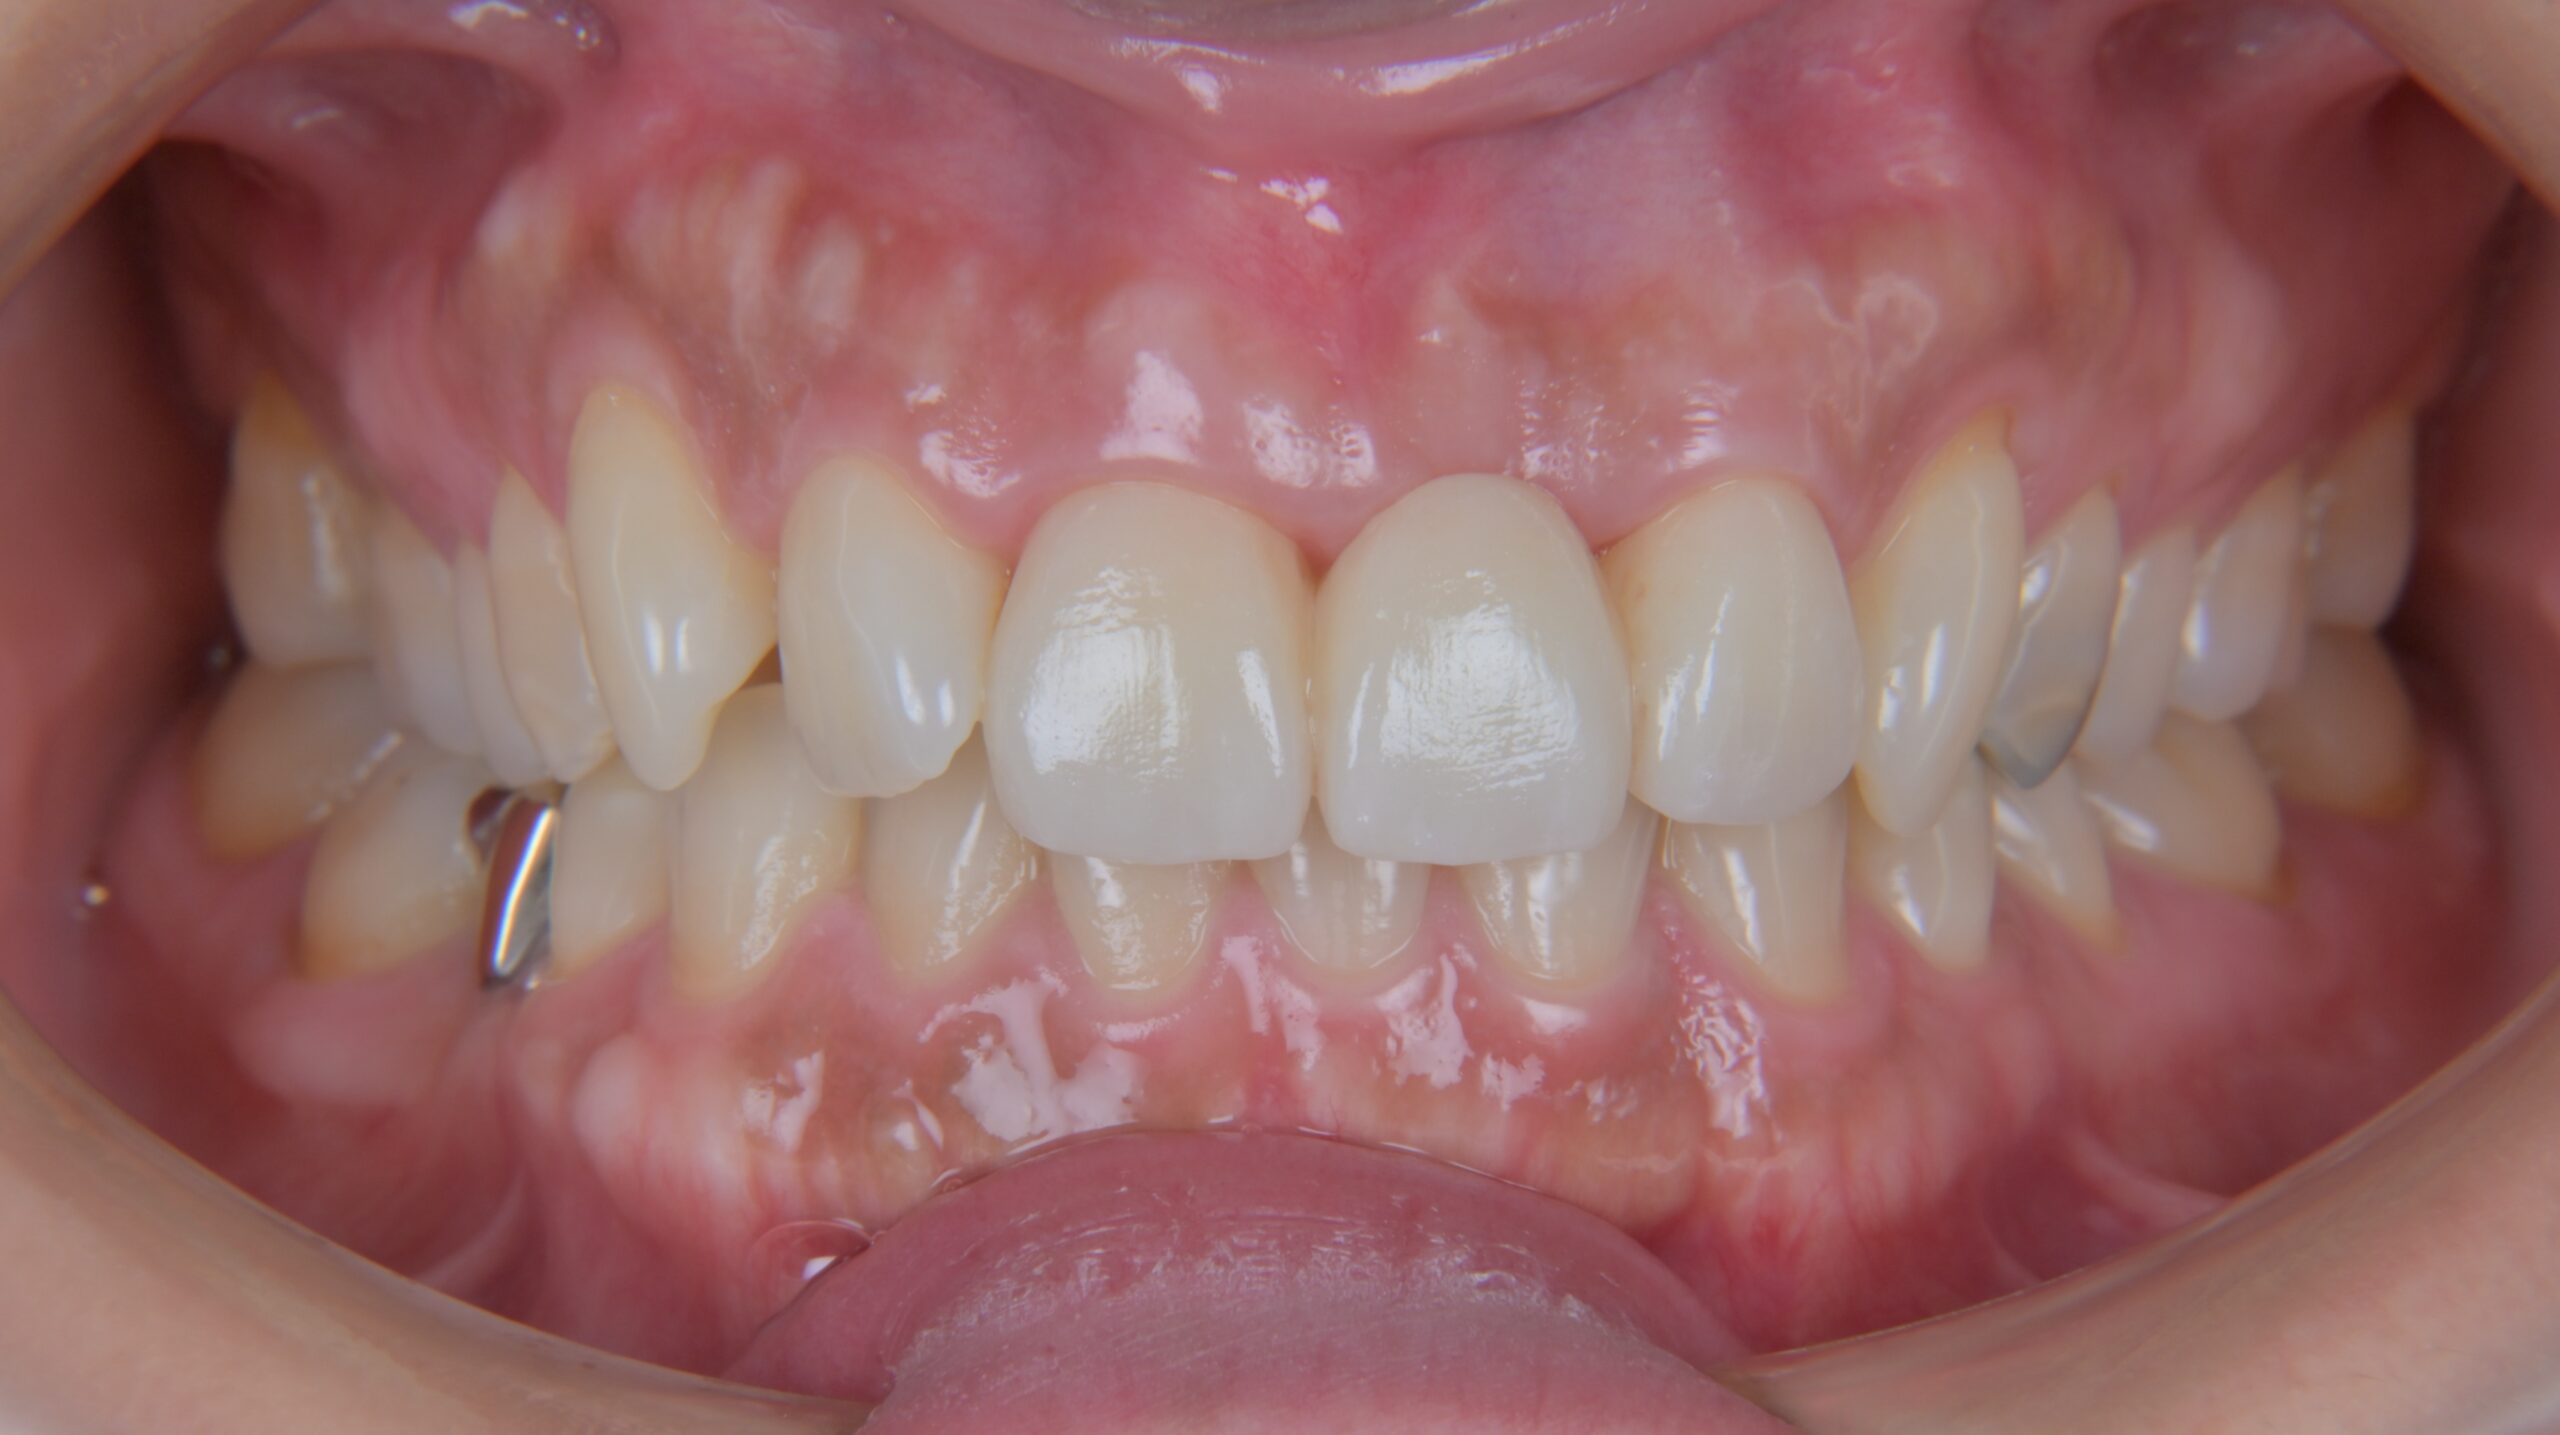

前歯のジルコニアクラウン症例

Before

After

治療内容

左上1番の被せ物に色の違いや、段差があるのが気になる為やり変えを希望されました。

古い被せ物を除去し、1回目の仮歯に置き換えます。

患者様と相談し形態を修正し、2回目の仮歯に移行します。

その後、最終的な被せ物を作るための型取りを行います。

最終的にジルコニアクラウンにて被せ物を接着しました。

担当歯科医師:平沼 佳朗

治療期間・回数

約3回

費用

¥154,000

リスク・副作用

ごく稀にジルコニアクラウンの先端が割れることがあります。